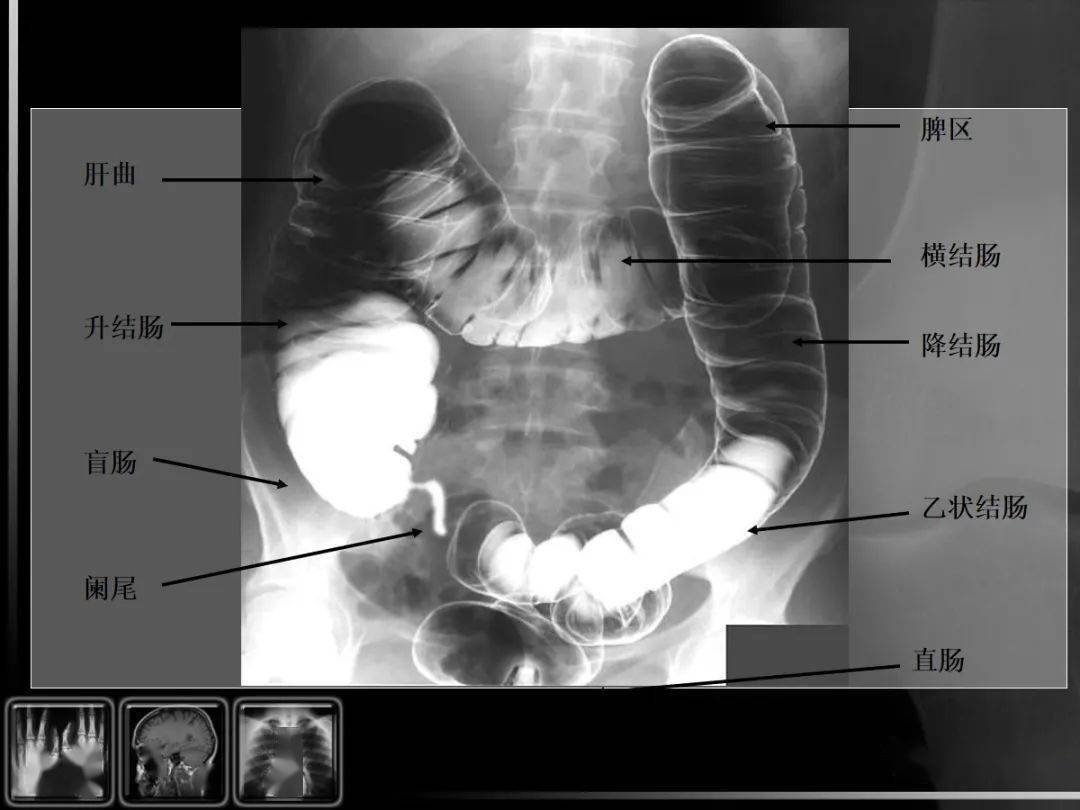

此次胃肠钡剂造影摄片如下: 诊断? 治疗?

图片尺寸1630x1130